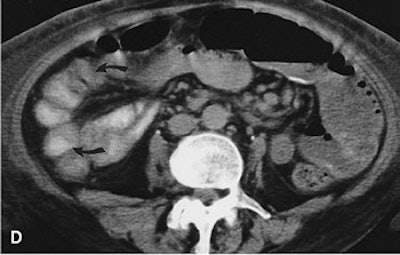

Similarly, Zalev and his co-investigators coupled CT with laparotomy. In one of Zalev’s case studies, a 60-year-old woman presented with multiple symptoms, including malabsorption. She had used NSAIDs for many years after bilateral total hip replacements. "A small-bowel CT scan showed a long jejunal segment with mucosal edema and multiple strictures," the authors wrote (Abdominal Imaging, January-February 1998, Vol. 23:1, pp. 40-44).

![]() |

| CT scan with oral and intravenous contrast through the plane of loop 3 (arrows) showing the strictures. Zalev, AH, Gardiner GW, Warren RE, "NSAID injury to the small intestine" (Abdominal Imaging, 1998; 23:40-44). |